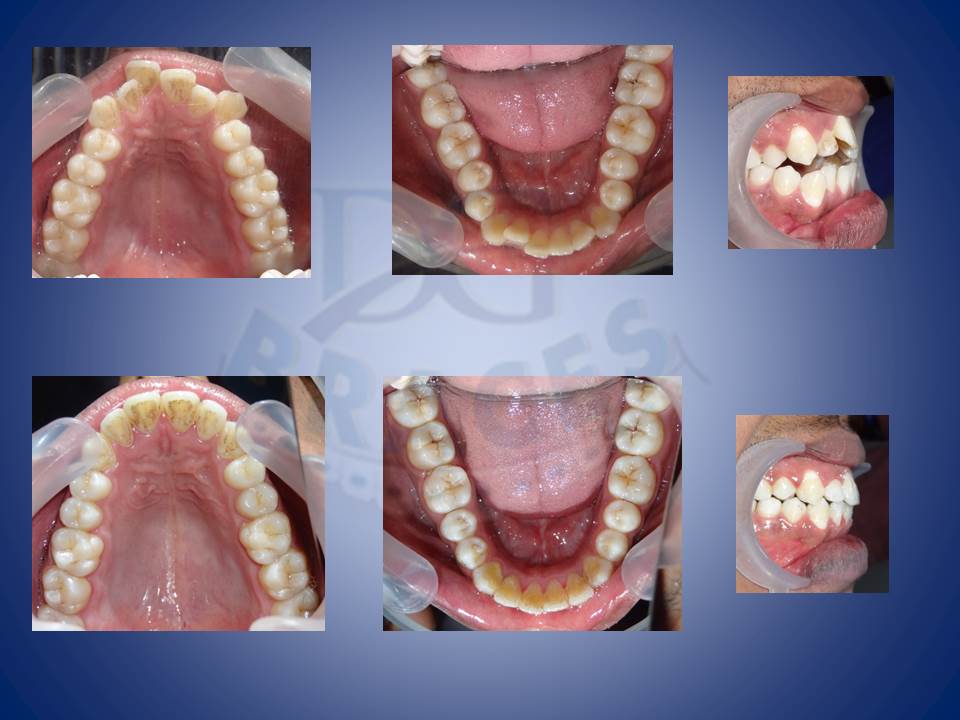

4.Dental spaces are better corrected witht the help of braces in comparison to artificial means like fillings and crowns.